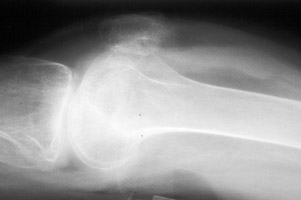

Fat fluid interface seen on the multiple lateral radiographs of the knee secondary to lipohemarthrosis. The fat-blood interface (FBI) is a very suggestive sign of underlying fracture extending into the joint. If no fracture is readily identified, diligent search should be undertaken.

Cross table lateral knee - Click on the image for a larger versionACross table lateral - Click on the image for a larger versionB